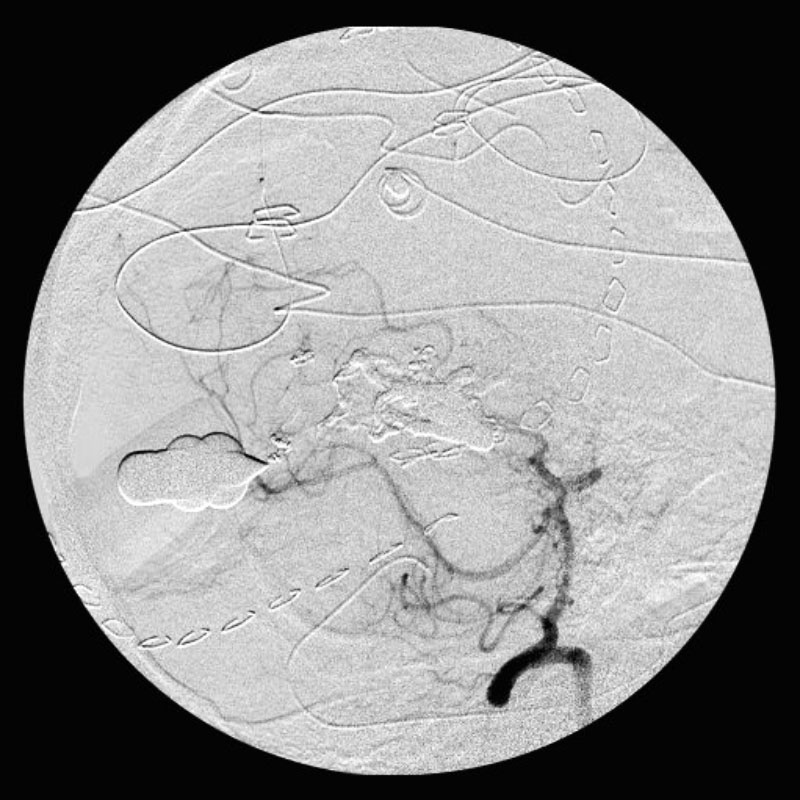

手術中

手術後